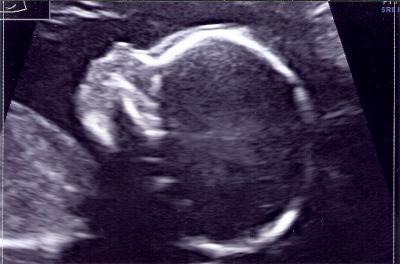

Hallo Mädels....es ist alles okay. Ich muss zwar in 5 Wochen nochmal hin, aber nur weil sie das Herz nicht richtig sehen konnte...unsere Zuckerschnute hat wohl was dagegen gehabt. Ist jetzt schon ne Diva =) Ja, es wird ein Mädel...aber pssssst...Joshua hat uns eine kleine Schwester für ihn geschickt =) LG Claudia

Oh nein ist das ein kleines süßes Mädel, echt sehr süß. Ich freue mich für euch. Und das alles gut ist noch viel mehr. Liebe Grüße Dana

so claudia...jetzt hast dus geschafft...gänsehaut und tränen in den augen :) ich freu mich so für euch und was für ein wunderschönes bild...so eine süße maus!!! meine daumen hast du immer! 6. monat wahnsinn...

Wow schon 6 Monat. Claudia ich freu mich so sehr, dass alles ok ist und glückwunsch zum kleinen Mädchen. Ich drücke euch weiterhin meine Daumen. LG